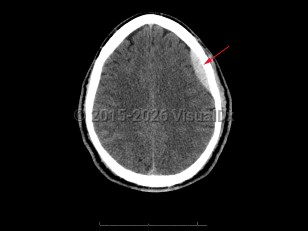

Subdural hematoma